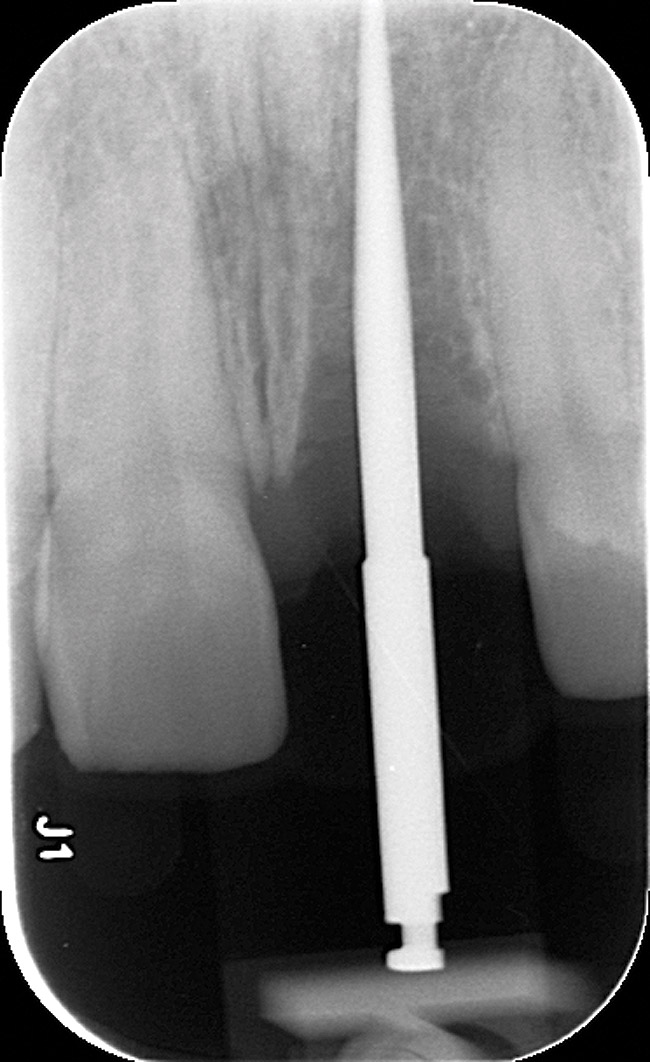

Figure 2  Initial periapical radiographs showing failed endodontic treatment of Nos. 24 and 25, and root resorption, No. 26.

Figure 2

Radiographic evidence of external root resorption on tooth No. 26 and periapical radiolucencies with a history of prior endodontic treatment, including apicoectomies, were present on the mandibular central incisors (Figure 2).